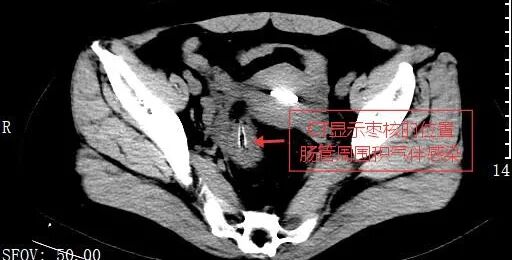

没思到腹部痛苦越来越强横,致使运转高烧不退。这下赵女士慌了,赶到温州医科大学附属金华病院(金华市东说念主民病院)急诊科就诊,完善相关查验后,被明确会诊为结肠穿孔和腹腔感染。

赵女士年级不算大,平淡排便风尚也挺好的,为什么会出现结肠穿孔呢?罪魁罪魁即是那一颗吞下去的红枣核!

急诊为赵女士安排了手术并取出了红枣核。因为腹腔感染严重,赵女士只可带着左下腹造瘘口生存了3个月,之后再回到病院进行下一步营救。